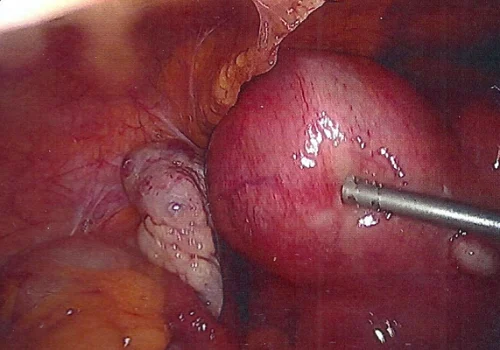

She had a large multi-fibroid uterus.

She subsequently underwent Total Laparoscopic Hysterectomy and removal of both Fallopian Tubes and Ovaries. The uterus weighed 670g.